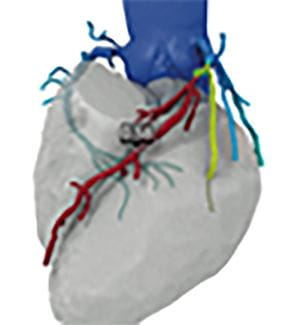

UH Harrington Heart & Vascular Institute Boasts Advanced Imaging Solutions

UH Clinical Update | October 2017